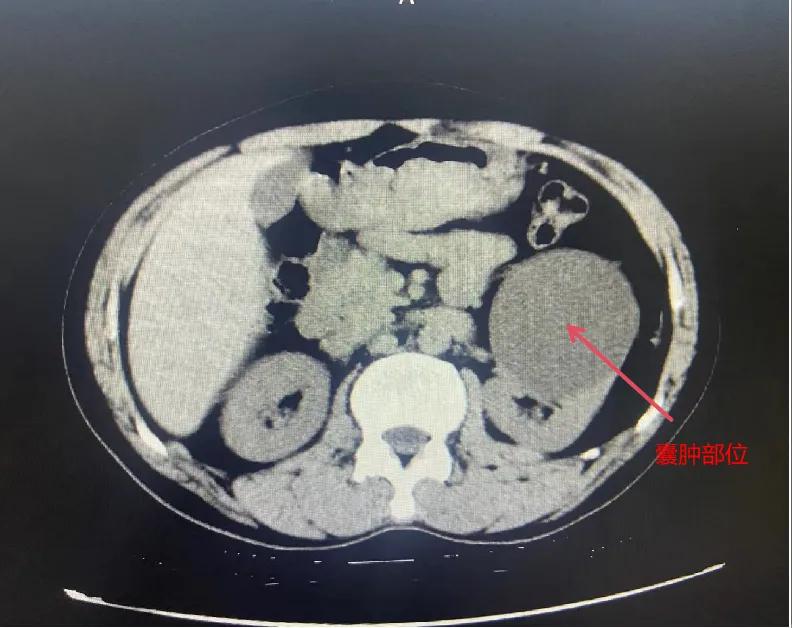

漯河市骨科醫(yī)院泌尿外科開(kāi)展后腹腔鏡下腎囊腫去頂減壓術(shù)

近日,漯河市骨科醫(yī)院(漯河醫(yī)專(zhuān)二附院、漯河市立醫(yī)院)連續(xù)收治2例腎囊腫患者。泌尿外科主任閆衛(wèi)甫和副主任醫(yī)師王金柱等醫(yī)師團(tuán)隊(duì)經(jīng)討論研究后,決定為患者采取后腹腔鏡下腎囊腫去頂減壓術(shù),經(jīng)過(guò)手術(shù)室、麻醉科等科室大力配合成功完成手術(shù)。

閆衛(wèi)甫表示,后腹腔鏡技術(shù)是一種微創(chuàng)外科手術(shù)方法,它通過(guò)在后腹腔(即腹膜后的空間)建立一個(gè)手術(shù)空間,利用腹腔鏡器械進(jìn)行手術(shù)操作。這種技術(shù)特別適用于泌尿系統(tǒng)等后腹腔臟器的手術(shù)。與傳統(tǒng)手術(shù)相比具有創(chuàng)傷小、恢復(fù)快、并發(fā)癥少、視野清晰等優(yōu)點(diǎn)。與前腹腔鏡相比則具有對(duì)腹腔臟器干擾較少的優(yōu)點(diǎn)。目前,后腹腔鏡手術(shù)主要用于腎囊腫去頂減壓術(shù)、腎上腺腫瘤切除、早期腎癌根治術(shù)、腎腫瘤剜除術(shù)等。

腎囊腫是一種常見(jiàn)的腎臟良性疾病,其發(fā)病率逐年增加。近年來(lái)隨著腹腔鏡技術(shù)的迅速發(fā)展,后腹腔鏡下腎囊腫去頂減壓術(shù)成為治療腎囊腫的主要方法。該手術(shù)具有創(chuàng)傷小,手術(shù)時(shí)間短,術(shù)中出血少,術(shù)后康復(fù)快,出院時(shí)間短等優(yōu)點(diǎn),并且術(shù)后復(fù)發(fā)率低,被認(rèn)為是治療腎囊腫的理想術(shù)式。(盧 闖 聶方方 劉 旭 袁錦鈺)